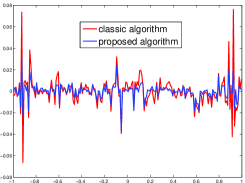

The reconstruction images from the noiseless projection data were shown in the Fig. 2. From Fig. 2, we can observe that the classic and the proposed algorithms can reconstruct images from the three projection data. In order to show the advantages of the proposed algorithm visually, the central vertical line of the differences between the reconstructed images and the original image are present in Fig. 3. We can observe that the -PP superiorization is more efficient than the classic superiorization in the aspect of suppressing the artifacts in the reconstructed images.

|

||

|---|---|---|

| (a) | (b) | (c) |